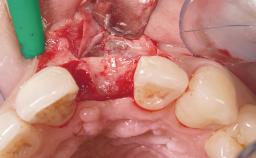

Late Flapless Placement of an Implant in a Maxillary Left Central Incisor Site

Bone Augmentation Horizontal|Staged

Augmentation Materials Xenogenous|Membrane